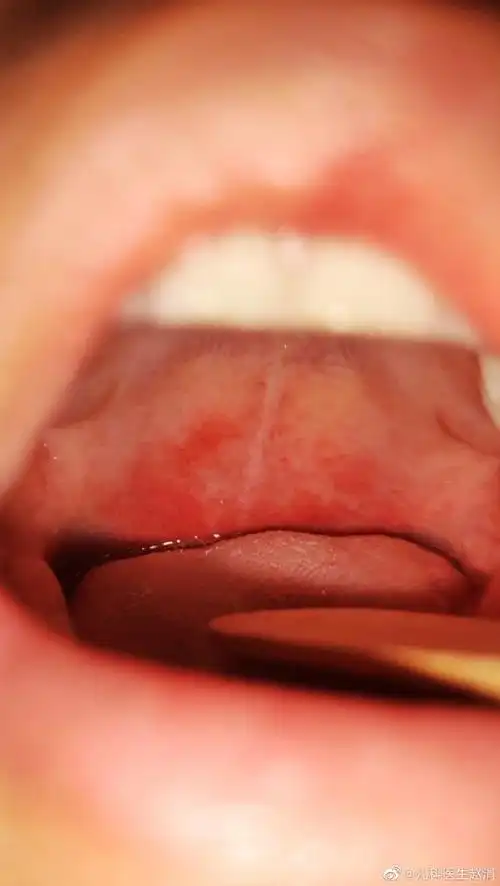

这充血的程度大家感受一下,特别是图一中软腭的充血,挺有特色,基本

图二:软腭瘀点【未被纳入标准的上腭瘀点】从上述 3 种标准可以看出

男孩六周岁,镜下所见,悬雍垂水肿,咽部粘膜充血,咽后壁淋巴滤泡增生